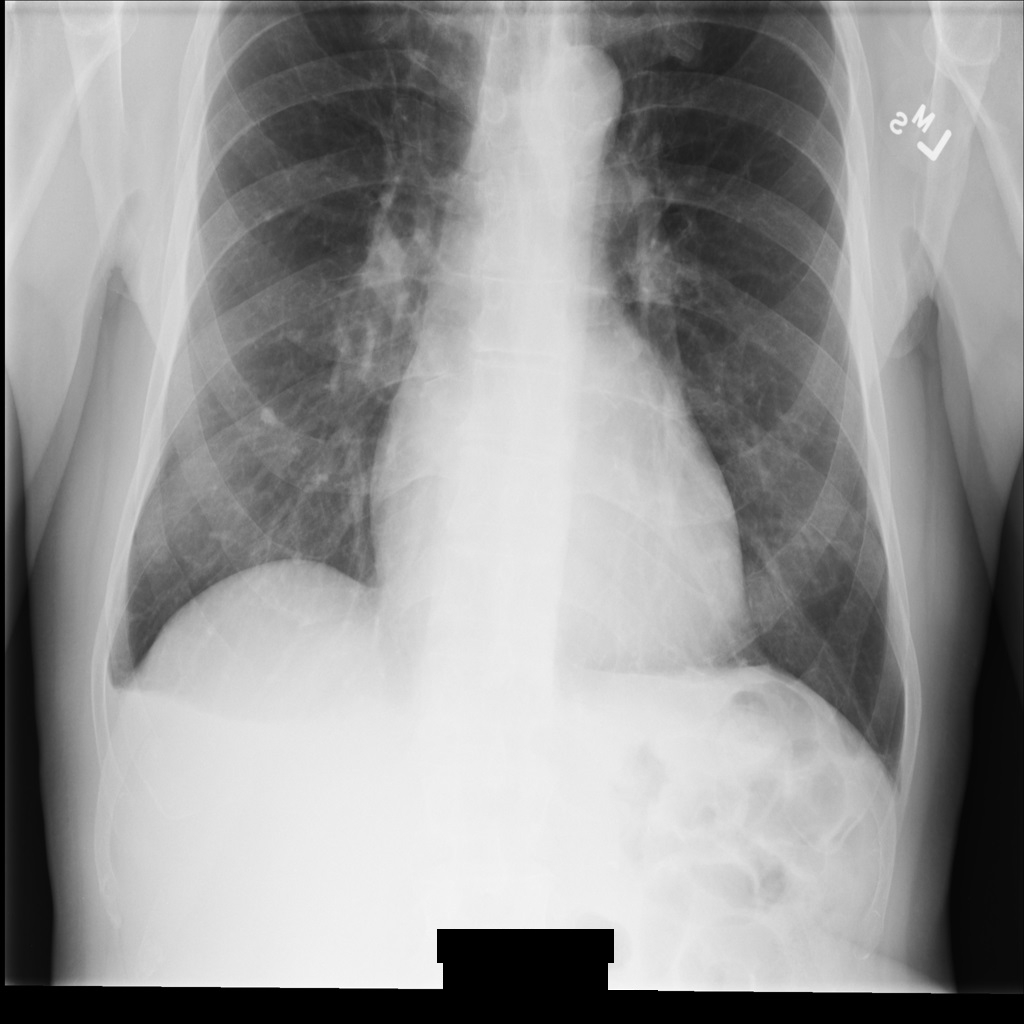

Sample image

Some samples in this page contain an output of the de-identified image. Each sample uses the following original image as its input. You can compare the output image from each de-identification operation to this original image to see the effects of the operation: